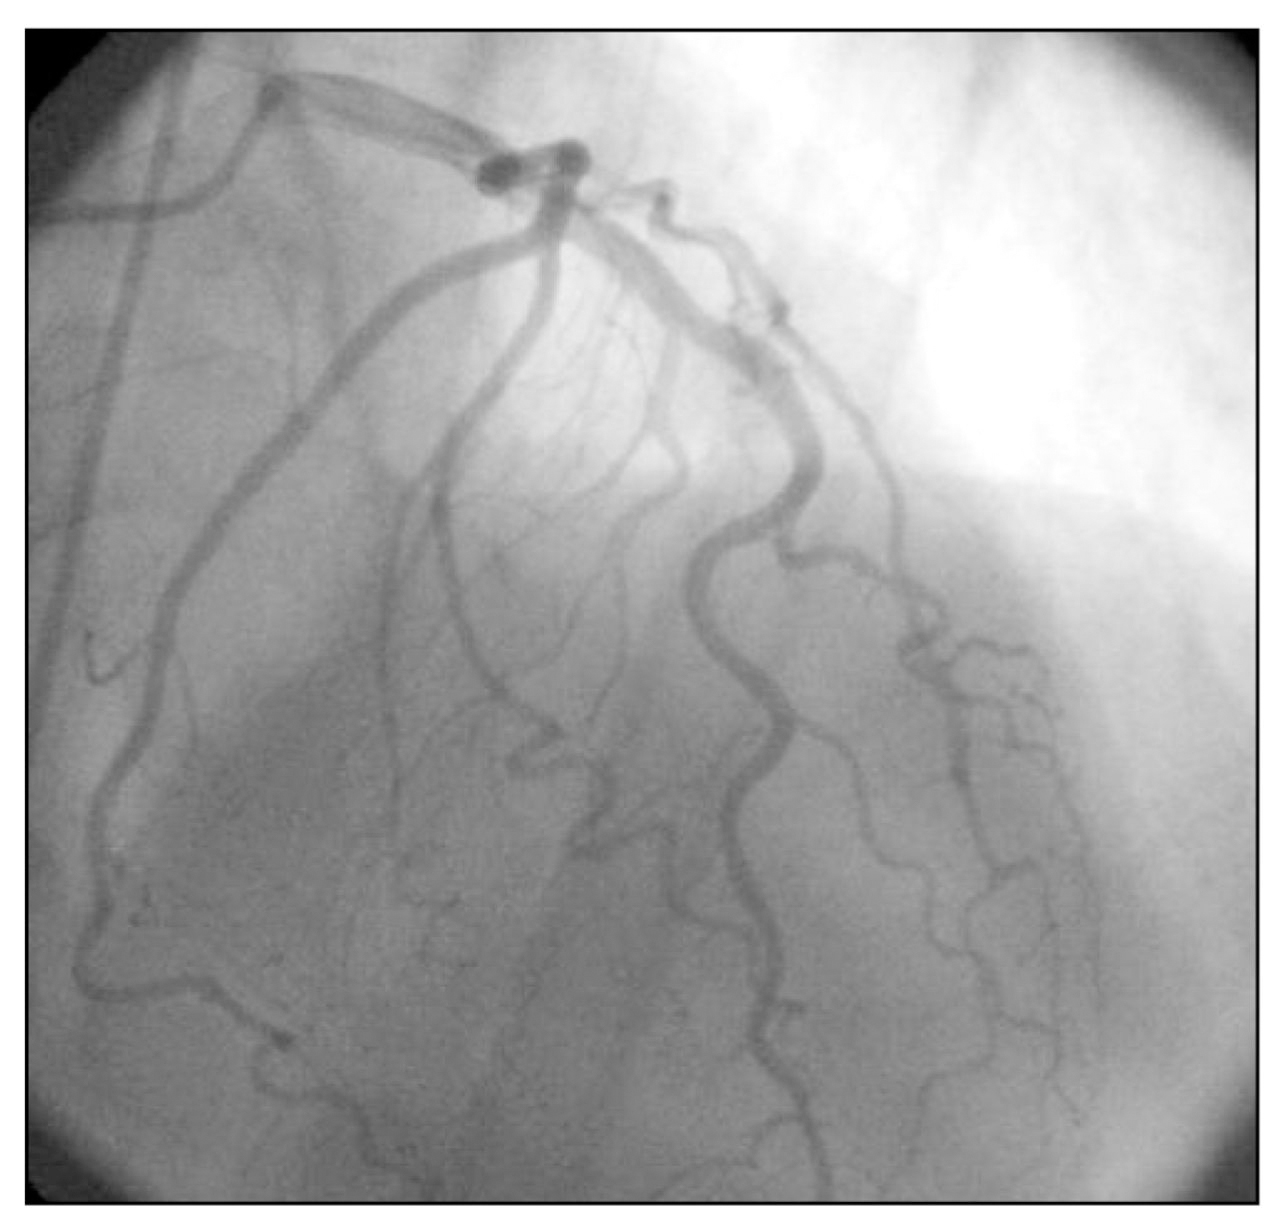

On the night of hospital day 1, the patient complained of midsternal chest pressure radiating to his neck. A second ECG demonstrated diffuse ST-segment elevation in the anterolateral and inferior leads, along with ST-segment depression in lead aVR and absence of ST-segment changes in lead V1 (Figure 1). Cardiac biomarkers revealed a creatinine kinase-MB fraction of 0.192 ng/mL and a troponin I level of 3.23 ng/mL. Immediate cardiac catheterization was performed (early morning of day 2), which revealed no new obstructive lesions in the patient's coronary artery anatomy (Figure 2). Ventriculography was deferred because of renal insufficiency and the recently performed computed tomographic pulmonary angiography. After cardiac catheterization, the patient underwent transthoracic echocardiography, results of which demonstrated a left ventricular ejection fraction of 30% to 40%, basilar hyperactivity, apical dyskinesia, and distal inferior and anterior akinesia (Figure 3).

Cardiac catheterization showing anatomy of the left coronary artery and its main branches. Minimal (<50%), nonobstructive coronary artery disease was noted.